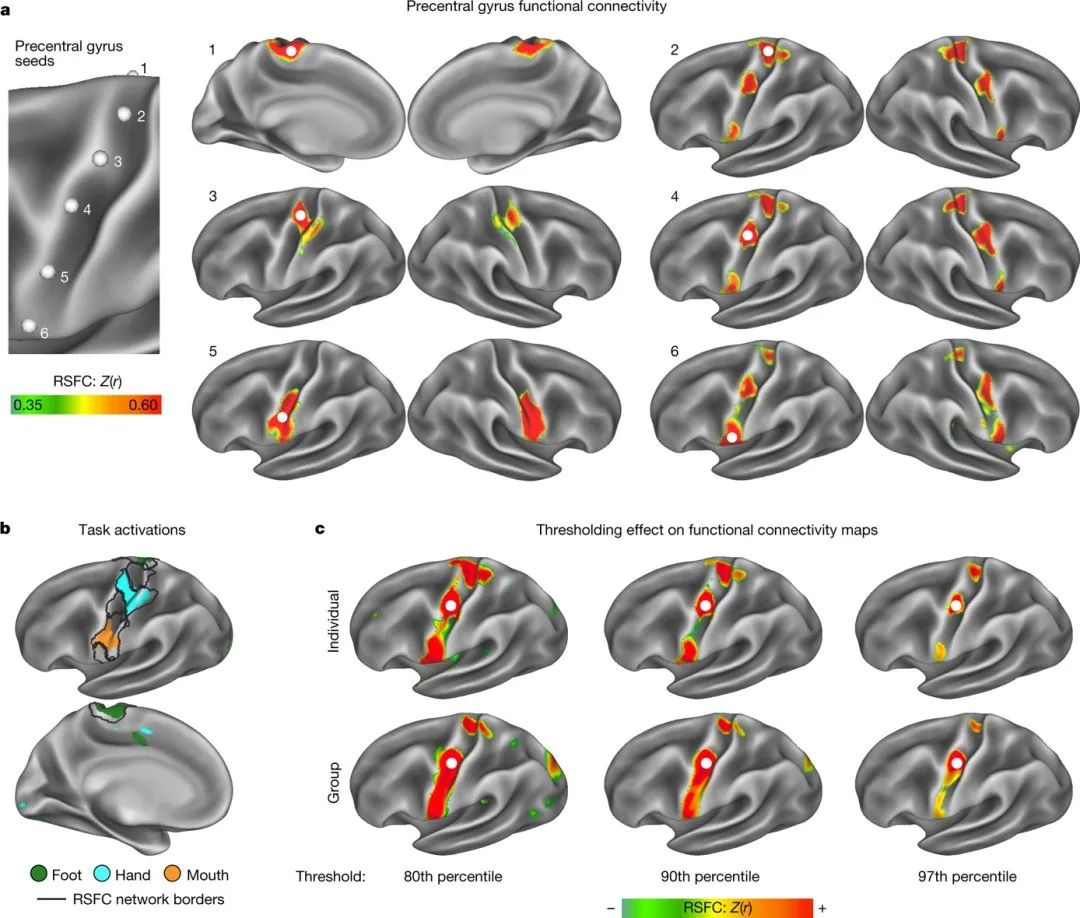

先进的PFM(Precision functional mapping)展示了M1与标准homuncular明显不同的连接性。M1中有两种对比鲜明的功能连接模式交替出现(图1a),其中包括预期模式(图1a,M1足,手,嘴)和一组未被识别(图1a seeds 2,4,6)的效应物间连接模式。这些区域在足部、手部和嘴部运动期间的任务诱发活动中表现出强烈的联系(图1-d)。结果表明,效应物之间的连接模式是M1的重要组成部分,这有助于进一步理解人类运动控制的神经机制。

图1.初级运动皮层的精确功能映射